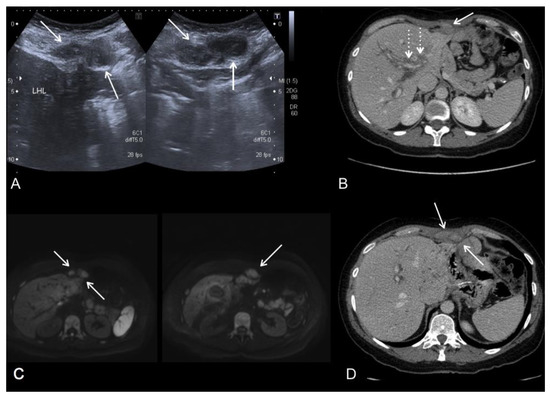

2.1. Computed Tomography (CT)

2.2. Magnetic Resonance Imaging (MRI)

2.3. Positron Emission Tomography (PET)-CT